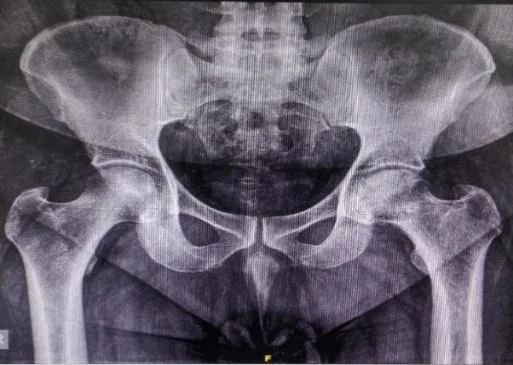

Digital X-Ray Pelvis with Both Hip Joint: True Size AP View

Digital X-Ray Hip Joint: Lat View

Digital X-Ray: Femur Whole Length with Knee Joint (AP/Lat view)

Digital X-Ray: L-S Spine Lateral View (Standing & Sitting)

CT Scan / MRI of Hip Joint (Reserve indication)